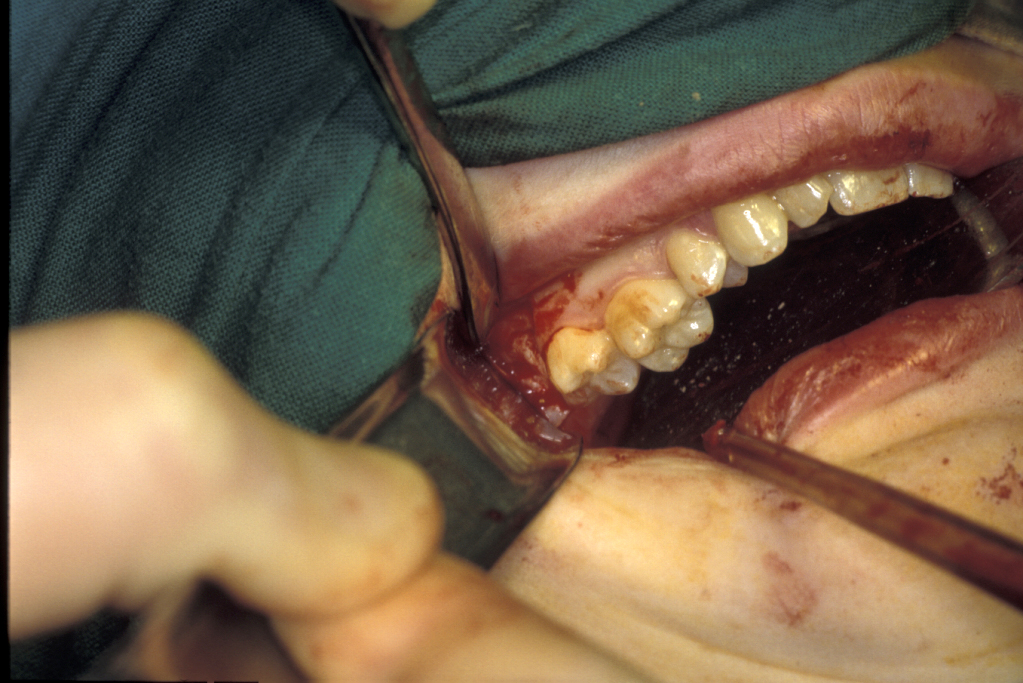

The principles of surgical removal are no different from those described for removal of retained roots. Accurate localization is essential as this affects the approach to the tooth, especially for upper canines. The vast majority are palatally positioned and therefore require a palatal flap for access. After the flap is raised, bone may have to be removed, either with chisels or a burr, and the tooth localised. It can be removed either en bloc or divided and removed in pieces. Extreme care needs to be taken not to damage adjacent roots. Occasionally the ‘broken instrument technique’ can be applied, passing the elevator through the buccal cortex or the nasal floor.